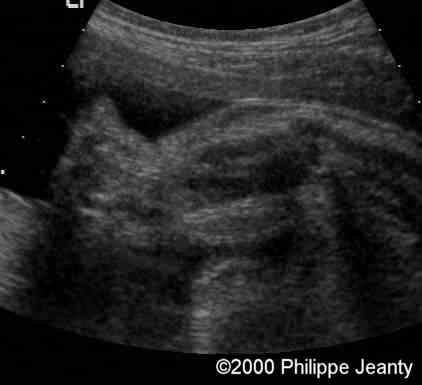

Humerus and femur (below) are too small (see chart below).

case0020-2

Femur

The femur (and humerus are way below the 5th percentile).